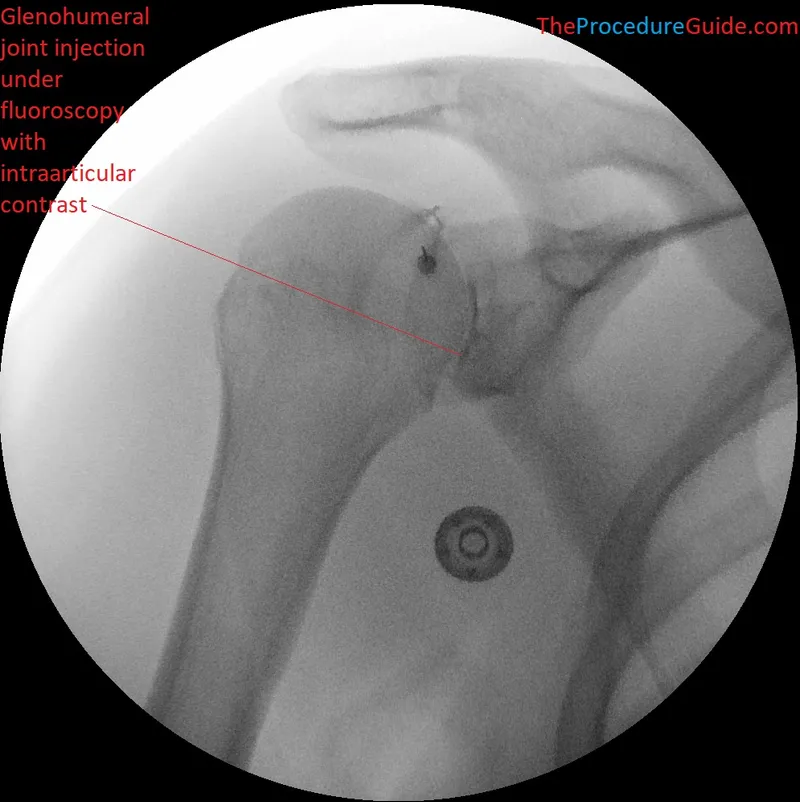

- Arthrography: Contrast (iodinated, gadolinium) injected into joint for imaging.

- Indications: Labral tears, ligament injuries, loose bodies, cartilage assessment.

- Types: Direct (contrast into joint), Indirect (IV contrast, delayed imaging).

Agent Examples Indications Notes Corticosteroids Triamcinolone, Methylprednisolone Osteoarthritis, inflammatory arthritis Anti-inflammatory, pain relief Local Anesthetics (LA) Lidocaine, Bupivacaine Diagnostic block, immediate pain relief Short-acting Viscosupplementation Hyaluronic acid derivatives (e.g., Hylan G-F 20) Osteoarthritis (knee) Lubrication, shock absorption; series of injections - Common Sites: Knee (suprapatellar, parapatellar), Shoulder (glenohumeral, subacromial), Hip, Ankle, Wrist.